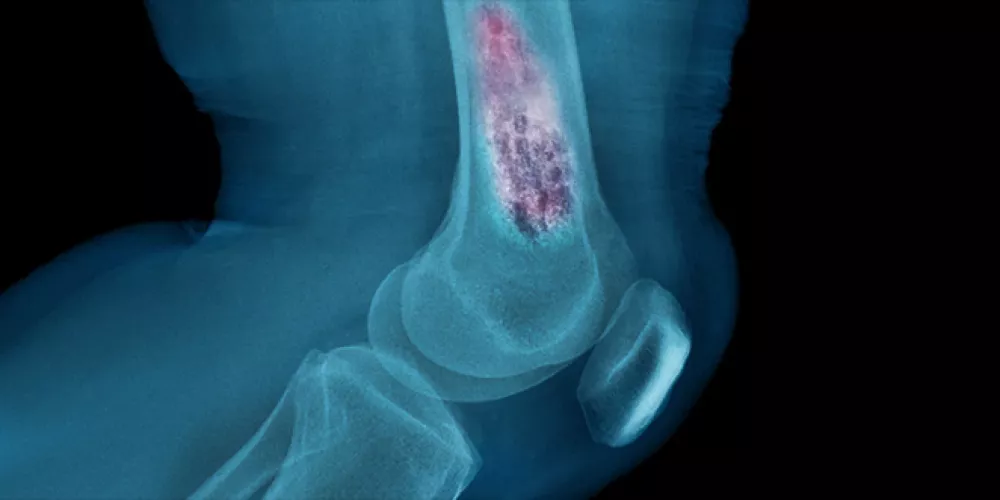

- الأشعة السينية

في المعتاد يستخدم الأطباء الأشعة السينية لتحديد أورام العظام، حيث يمكن أن تظهر هذه الأورام كـ “تمزق” أو ثقب في العظام وفي بعض الحالات، يمكن مشاهدة الورم وهو يمتد إلى الأنسجة المجاورة، مثل العضلات والدهون ومع ذلك، جرت العادة على إجراء خزعة لتأكيد التشخيص؛ بالإضافة إلى ذلك يستطيع الأطباء إجراء فحص للصدر باستخدام الأشعة السينية للتحقق من عدم انتقال السرطان إلى الرئتين، لكن يمكن استخدام التصوير المقطعي المحوسب كبديل لهذا الفحص لدى البالغين الذين لديهم أورام في العظام.